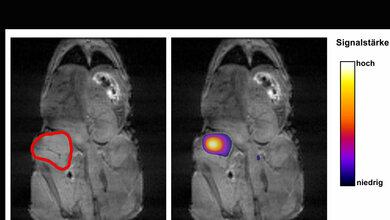

Doch auch bei der Diagnostik geht es mit Riesenschritten voran. Neben den neuen Möglichkeiten in der Bildgebung ist hier beispielsweise Liquid Biopsy ein Schlagwort. Die Nukleinsäureanalytik zum Nachweis von Tumorzellen und Tumor-DNA sorgt für Furore.